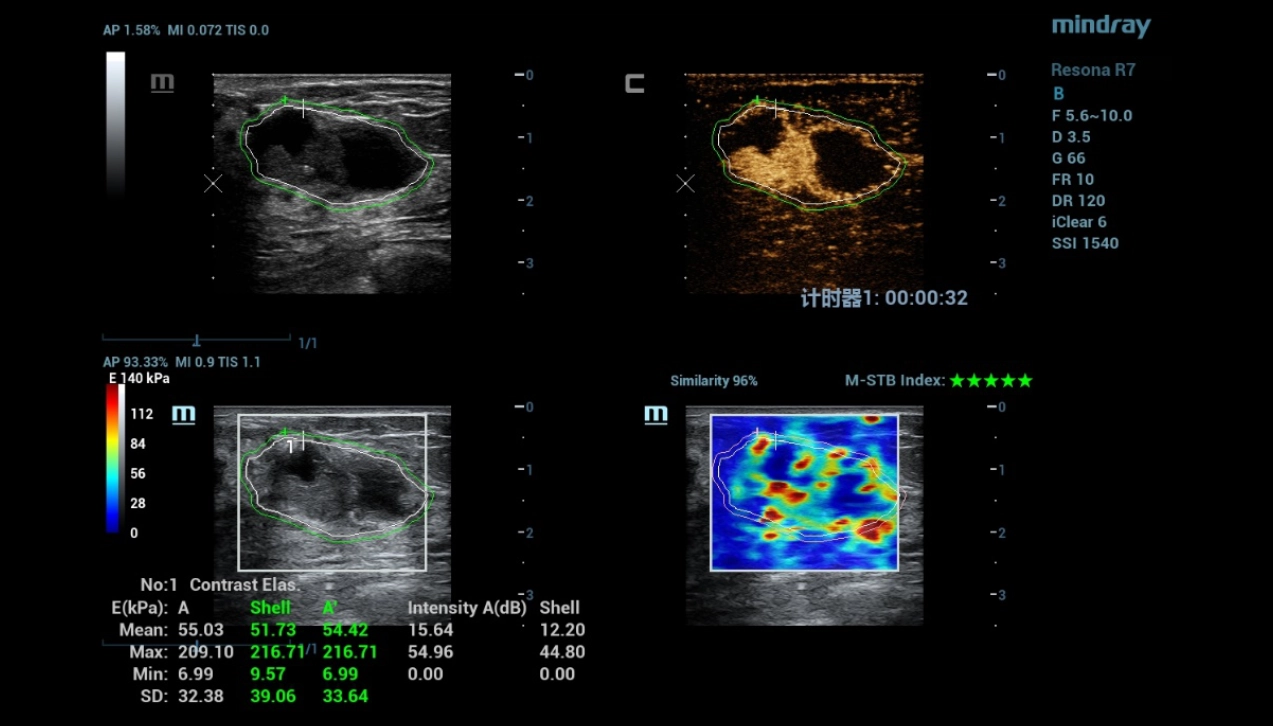

A 53-year-old woman seeks medical help for compaction and pain in the left breast. During ultrasound examinations, different imaging techniques were used to provide a more comprehensive analysis.

According to the B mode and STE, the focal formation of the breast was characterized as benign. In Doppler mode, there were signs of suspected neovascularization. Contrast ultrasound demonstrated increased vascularization of the formation with slow washout of the contrast agent. The quantitative analysis made it possible to objectify the data of qualitative analysis in the form of time-intensity curves and quantitative parameters. Finally, the multiparametric approach made it possible to exclude neovascularization detected by Dopplerography.

Based on these ultrasound findings, a benign phylloid breast tumor was diagnosed according to the results of the histological examination.

Tissue stiffness and perfusion details vary between the malignant tumor and the benign. M-Ref. C&E connects the contrast and STE to one plane, for a complete assessment of the lesion boundary and range of infiltration.

multi-parametric-imaging-fig9-pc

M-Ref. C&E